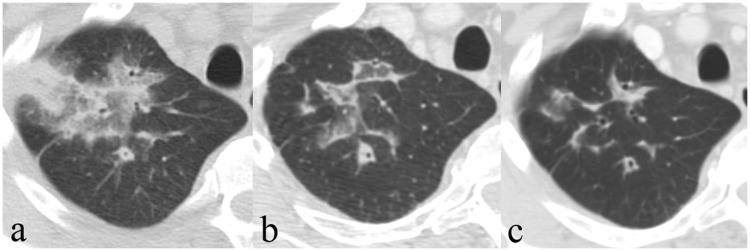

In our cohort, ground glass opacity was the most common imaging pattern (17/17, 100%) in patients with OP followed by a reticular pattern (12/17, 71%), consolidations (10/17, 59%), nodules (7/17, 41%), crazy paving (5/17, 29%), bronchi(ol)ectasis (4/17, 24%), focal mass (3/17, 18%), and reversed halo (1/17, 6%). The most common imaging pattern was changing multifocal consolidations (8/17, 47%). A bronchocentric and a nodular pattern were found in four patients (24%) each, a progressive fibrotic pattern in none patient, and reversed halo/atoll pattern in one (6%) case.

在我们的队列中,磨玻璃影(17/17,100%)是OP患者最常见的影像学表现,其次是网状影(12/17,71%)、实变影(10/17,59%)、结节影(7/17,41%)、铺路石征(5/17,29%)、支气管(细支气管)扩张(4/17,24%)、局灶性肿块(3/17,18%)和反晕征(1/17;6%)。最常见的影像学表现是多变性多灶性实变(8/17,47%)。4例患者(24%)出现支气管周围型和结节型表现,无患者出现进行性纤维化型表现;1例患者(6%)出现反晕/环礁征表现。